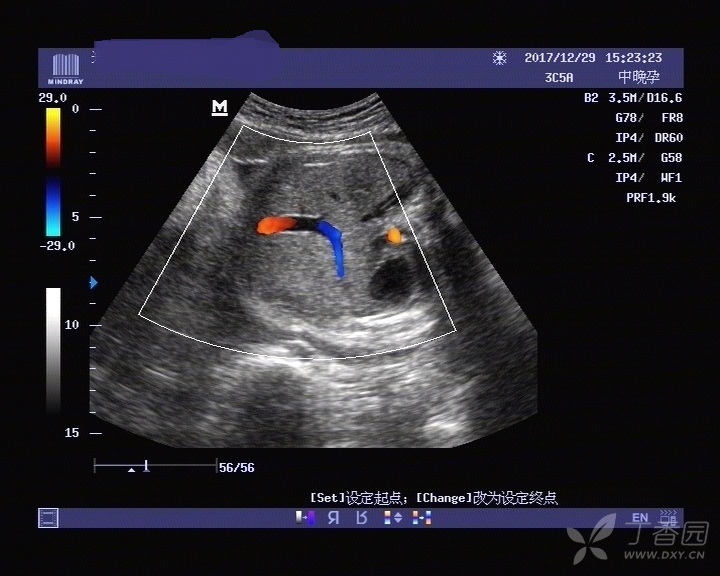

这是永久性右脐静脉吗?

图片尺寸720x576